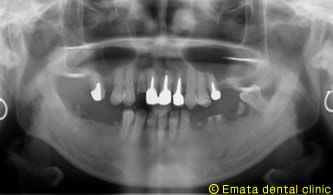

患者さんは女性のかたで、前歯がとれてしまい、このさい前歯を綺麗に治したいと来院しました。

お口の中を診査しますと、奥歯はほとんど崩壊状態でした。

患者さんに一口腔単位での治療が重要性をご説明し、奥歯をしっかり治療することにしました。